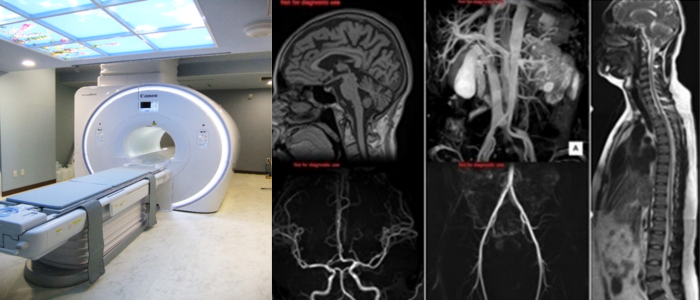

MRI

- Canon Vantage Orian 1.5T

強力な磁石でできたトンネル型の装置に入り、磁気の力を利用して体の臓器や血管を撮影する事ができます。

特に脳や、脊椎、関節、腹部から骨盤内の病変に対して優れています。

また造影剤を使用しなくても血管の撮影を行うことができます。(検査によって造影剤を使用する事もあります)

放射線科の中で唯一放射線を使用しない装置であり、被ばくの心配がありませんが、撮影室内は非常に強い磁力が発生しているため、着替えや装飾品の取り外しやお化粧の制限、事前の問診にご協力を頂いています。